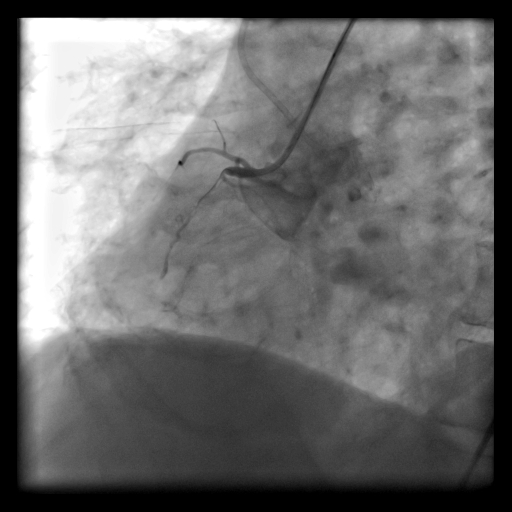

Koroner arterin %100 (tam) kronik olarak tıkalı olduğu (CTO) vakalarda damarın açılması çok zor iken, gelişen kılavuz tel teknolojisi ile oldukça kolaylaşmıştır. Bu gün itibariyle başarı oranı %70 civarındadır ve her damarı tam tıkalı olanda değil, açma işleminin faydalı olacağı (!) grupta bu işlem planlanmalıdır.

- Kronik Tam Tıkalı Kalp Damarında Balon/Stent İşlemi